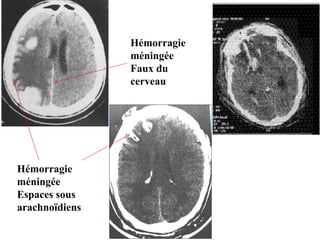

Hémorragie méningée

Elle peut être secondaire à une lésion

vasculaire méningée ou suffusion

hémorragique à partir d’un foyer de

contusion cérébral.

TDM (SPC): hyperdensité spontanée des

espaces sous arachnoidiens et des

citernes. Elle peut être diffuse ou localisée.

Hémorragie sous-arachnoïdienne

Hémorragie

méningée

Espaces sous

arachnoïdiens

Faux du

cerveau